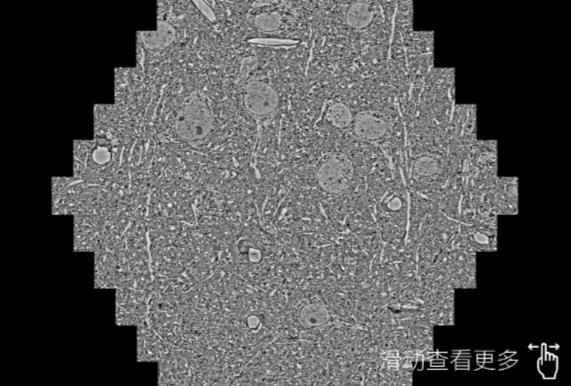

鼠脑切片。左图使用宝山蔡司宝山扫描电镜MultiSEM706对165μmx143pm面积区域成像,耗时仅需1.5秒。右图为鼠脑切片中30μm区域放大效果。样品由芝加哥大学B.Kasthuri提供。

使用蔡司高速宝山扫描电镜MultiSEM对1mm²人脑皮层组织进行高分辨成像,并对其中的各种细胞结构进行三维重构分析。左图展示了2x3mm²组织平面中锥体神经元的三维重构效果。右图显示了局部体积神经元三维重构。图像由哈佛大学chtman实验室提供,渲染图由D. Berger 制作。